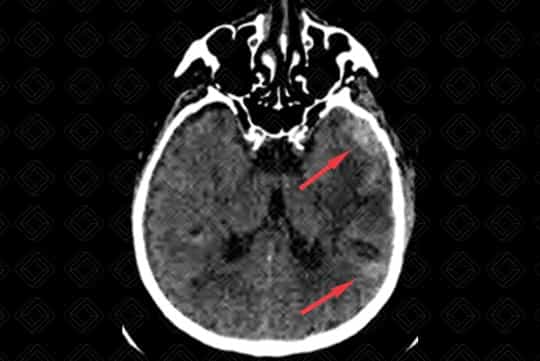

Texto alternativo para a imagem Figuras 1 e 2. Créditos: Dra. Elazir Mota - Rio de Janeiro/RJ

Descrição da lesão (figuras 1 e 2): Tomografia computadorizada de crânio sem contraste venoso. Áreas de hemorragia subracnoide córtico-subcorticais nas regiões temporal esquerda e temporo-parietal direita (setas vermelhas). Há ainda moderada hiperdensidade do seio reto e tentório cerebelar, sugerindo sangramento (setas brancas).